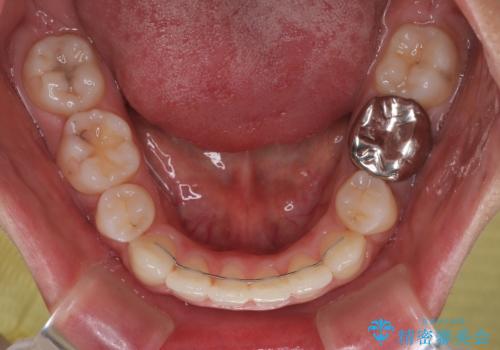

途中出産や育児があり、治療期間長くなってしまいましたが、ストレスなく唇が閉じられるような口元に仕上げることができました。